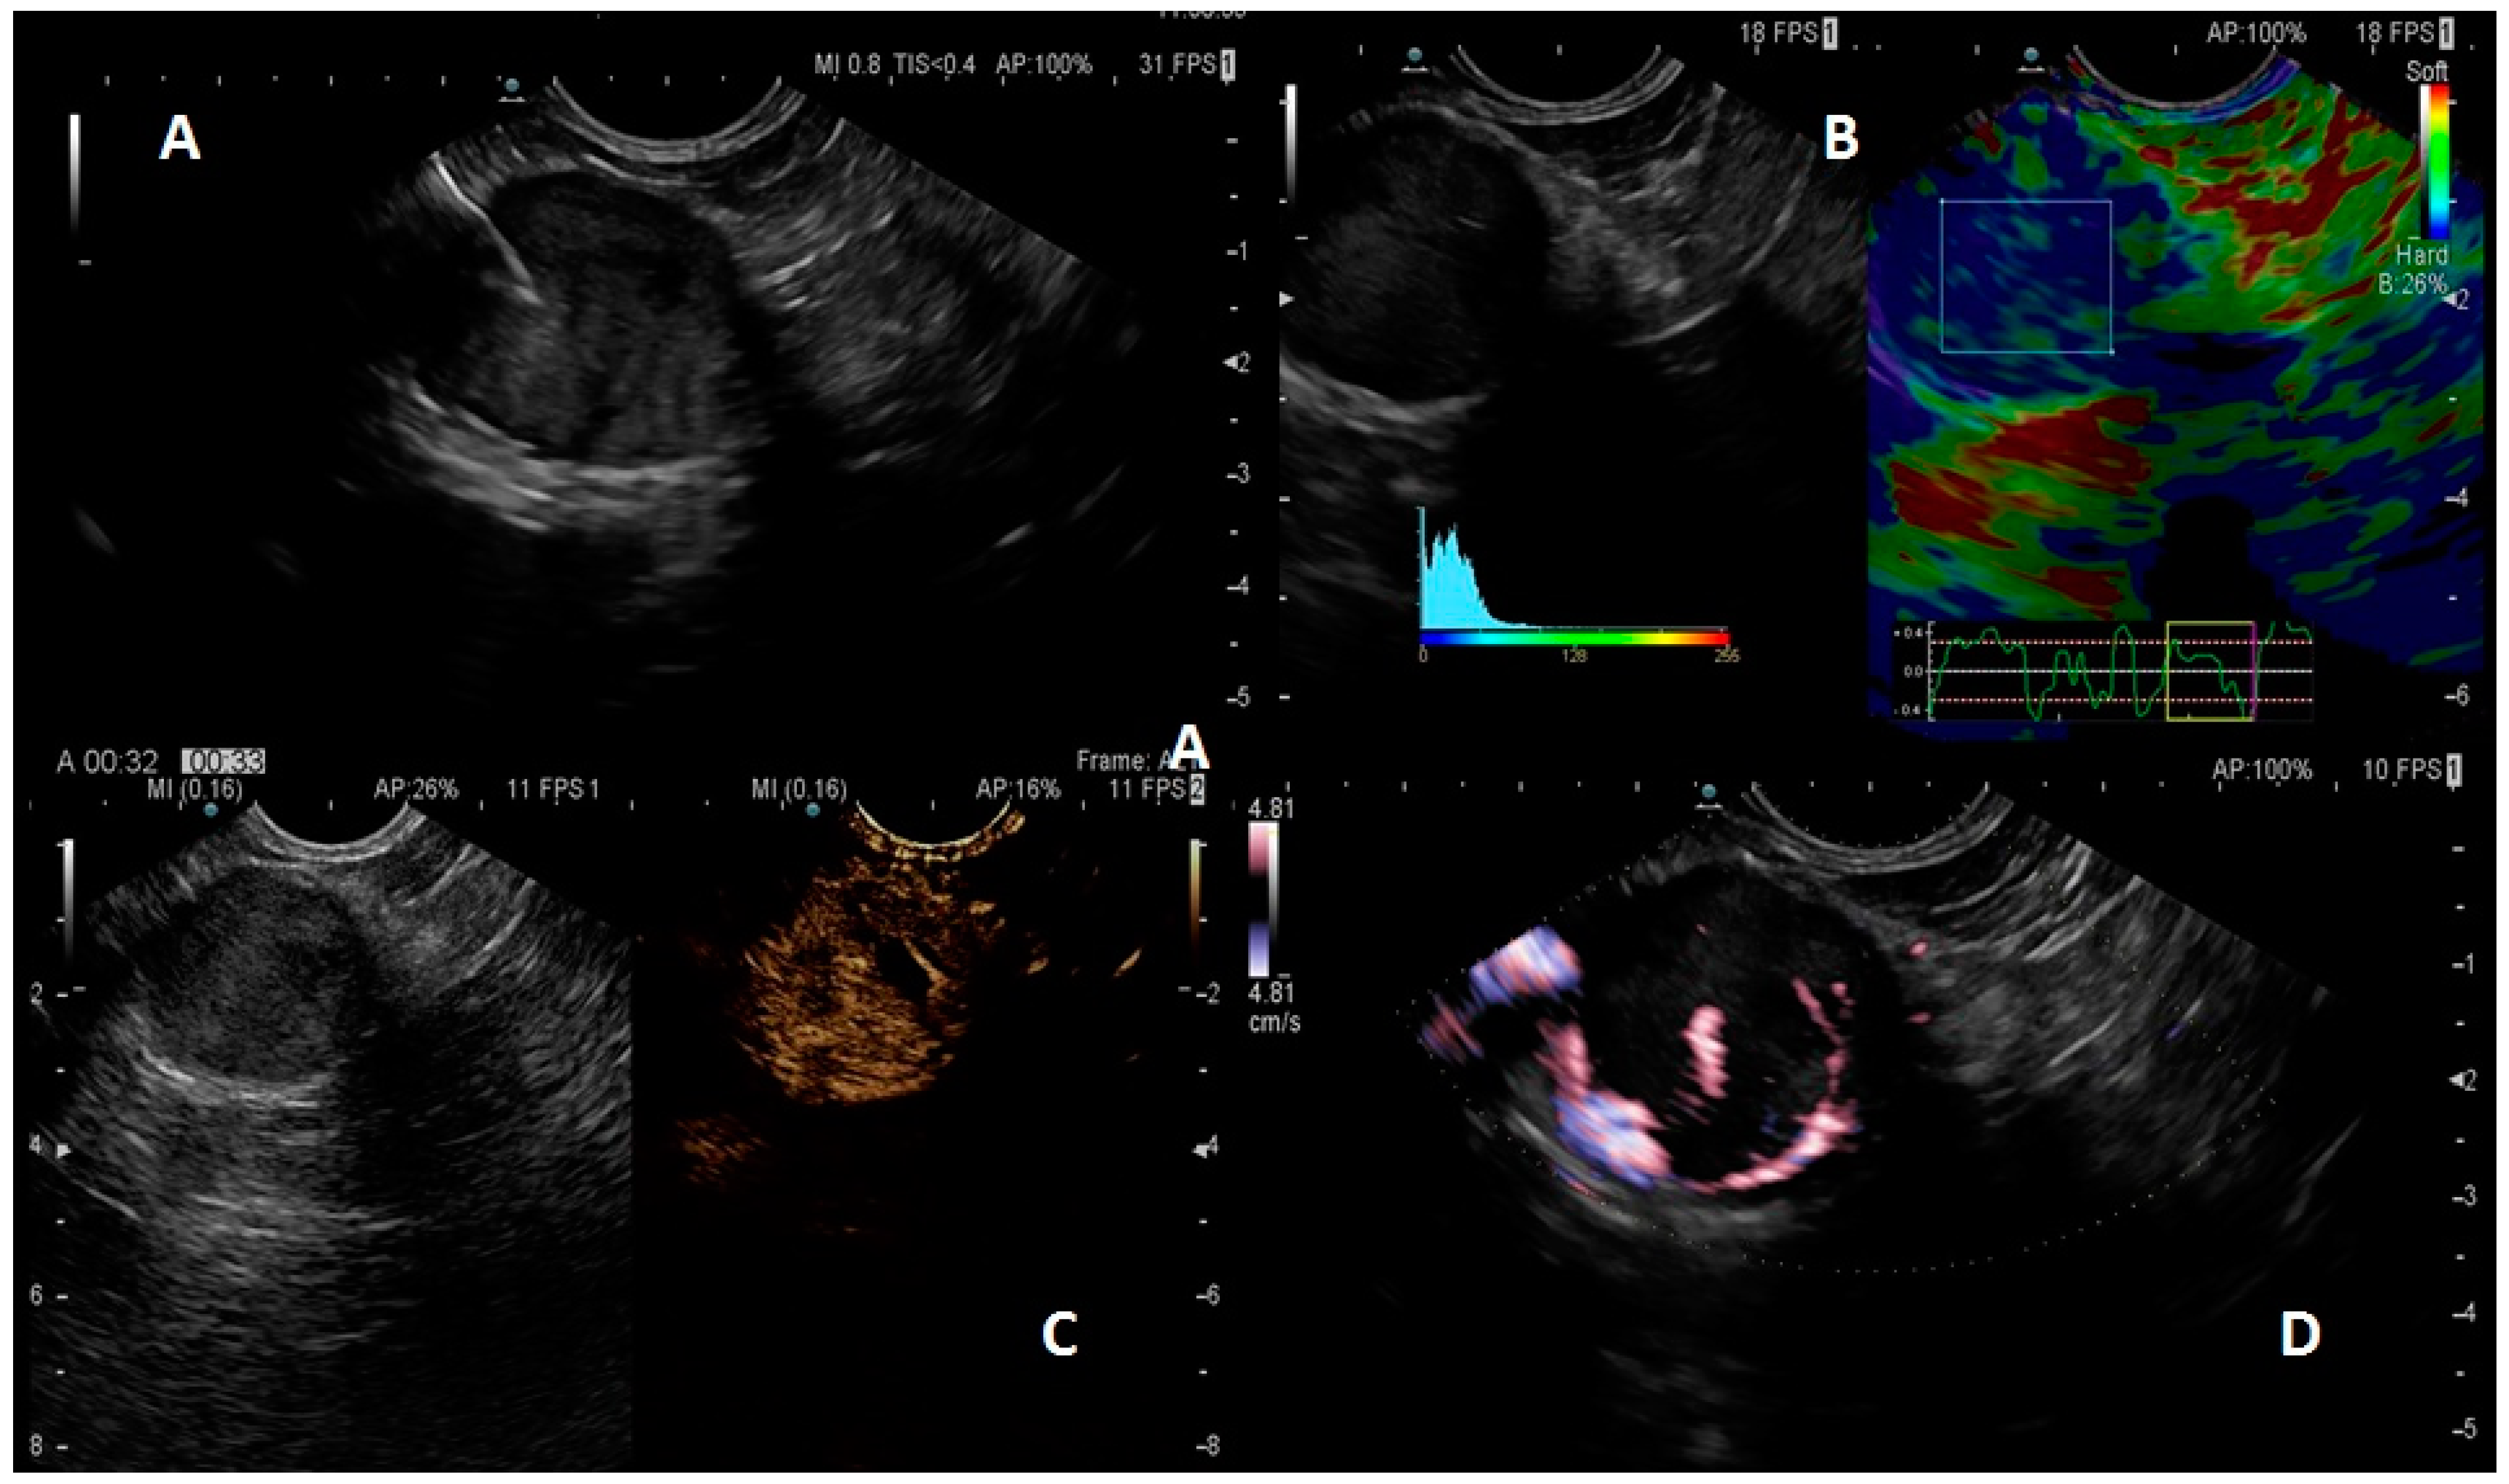

In general, a well-differentiated pNET appears in EUS as a hypoechoic lesion with well-rounded margins, hypervascular in Doppler imaging, with a vascular rim at the margins of the lesion, and rigid in elastography (an applied software which can assess tissue stiffness). After intravenously contrast-enhanced EUS (CE-EUS), a pNET shows a fast uptake of the contrast and a rapid consequent wash-out (Figure 1).

Figure 1. Pancreatic neuroendocrine tumor (pNET) aspect. B-mode (A): hypoechoic lesion with well-defined margins; qualitative and semi-quantitative elastography; (B): pNET as a stiff, blue lesion; pNET at intravenous contrast; (C): early hyperenhancement of the contrast; pNET aspect at power Doppler (D), with a peripheral vessel capsule.